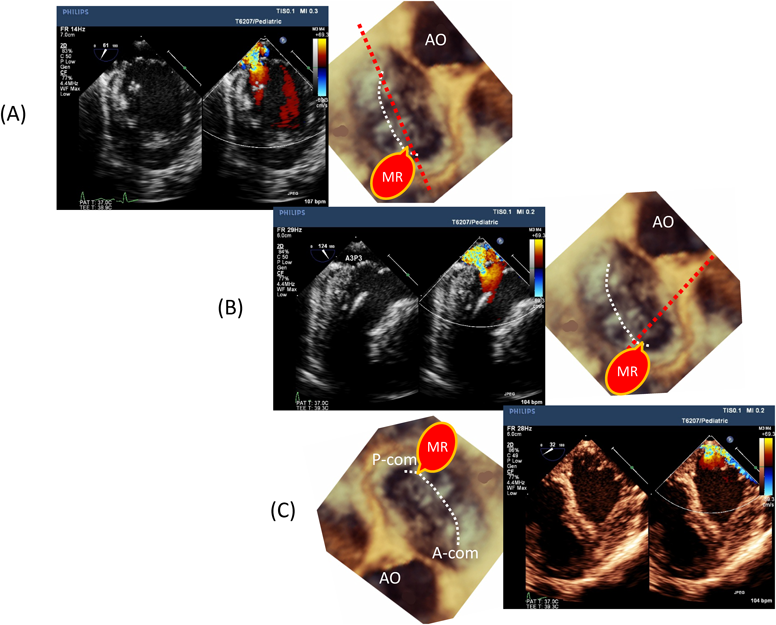

Fig. 3 Mid-esophageal view of a transesophageal echocardiography

(A) Mid-esophageal four-chamber view at the anterior commissural level. (B) Mid-esophageal four-chamber view at middle of the mitral valve. (C) Mid-esophageal four-chamber view at the posterior commissural level. Note significant mitral valve regurgitation at the posterior commissure. A-com: anterior commissure; AO: aorta; MR: mitral regurgitation; P-com: posterior commissure.

Pediatric Cardiology and Cardiac Surgery 33(2): 140-156 (2017)

Fig. 4 Mid-esophageal and transgastric view of the mitral valve

(A) Mid-esophageal mitral commissural view. (B) Mid-esophageal long-axis view at the posterior commissure. (C) Transgastric basal short axis view. Note the significant prolapse of A3 with significant mitral valve regurgitation. The echogenicity of the basal-inferior endocardium and the posteromedial papillary muscle are increased. A-com: anterior commissure; AO: aorta; MR: mitral regurgitation; P-com: posterior commissure.

小児では経胸壁エコーにて良好な画像が得られやすいこと,またTEEが全身麻酔を必要とすることなどから,成人に比してTEEが行われる機会は少ない.しかし,弁形成術の際には術前の最終評価をTEEで行うことが望ましく,経胸壁心エコーとは異なった角度から観察することにより新たな所見を発見することや,既に得られていた弁機能異常のメカニズムについて更に深い観察が可能となることがある.そして,できれば外科医と一緒に所見の最終確認を行うべきである.現在,使用されている成人用matrix TEEプローブは体重25 kg以上であれば小児でも使用できることが多いが,先端サイズが横幅約15 mm/厚さ12 mm程度(シャフト軸径は9~10 mm)と大きいことから,口腔内容積が小さい場合や咽頭の解剖に懸念がある場合,または食道内へ挿入した際に呼吸器の気道内圧が上昇する場合などには,無理せず小児用のTEEプローブ(先端サイズ幅約10 mm/厚さ8 mm・シャフト軸径6.7 mm)を使用する.小児用のomni-plane TEEプローブは体重5 kg以上であれば使用可能なことが多い.なお,先に記したTEEプローブのサイズは代表的なメーカーのomni-planeのサイズであり,メーカーによってはomni-plane TEEプローブの更に小さいものや,bi-planeもしくはsingle-planeの更に細いTEEプローブを提供しており,これらは5 kg以下の乳児にも使用可能である.しかし,3 kg以下になるとやはり換気や血行動態への影響の懸念が強くなることから,その適応を慎重に判断する必要がある.また,胃・食道術後(食道閉鎖術後など),食道狭窄,食道静脈瘤・潰瘍・腫瘍・憩室,傍食道型食道裂孔ヘルニア(滑脱型食道裂孔ヘルニアは必ずしも禁忌とはされていないが,高度のヘルニアで通過障害を来している場合はやはり禁忌と考えられる)の場合には経食道心エコー検査は禁忌である.また,頸椎の可動性低下を認める場合や頸部への放射線治療後も禁忌であることから,検査前に慎重な既往歴の確認が必要である7).更に,著明な左房拡大や肺静脈狭窄などを合併しており,経食道プローブを挿入することで血行動態に悪影響を及ぼすことが予想される場合も適応を慎重に判断する必要がある.僧帽弁評価に使用する断面は中部食道(mid-esophageal: ME)と経胃断面(trans-esophageal: TG)が多い(Fig. 2).ME四腔断面(0度)(Fig. 3)は各心腔が確認でき,弁逆流や狭窄の程度を観察するのに適している.心臓の胸腔内での位置関係にもよるが,少し後屈させて心室が長軸方向に長く描出されるように調整する.ただし,後屈を強くしすぎると食道壁との接触が不良になり画質が低下する.また,この角度で得られる画像はFig. 3に示す通り,僧帽弁を少し斜め切りすることになることから,前尖のA2を観察していても後尖はP1に相当する可能性があり,診断する際には注意が必要である.プローブの出し入れにより,前交連から後交連までの連続した観察を行う.Fig. 3にPAIVS(pulmonary atresia with intact septum)に類洞交通を合併した3歳児例のカラードプラ画像を示す.BTシャント手術の際に下壁および後乳頭筋の心筋梗塞を合併し,以降よりA3のprolapseによる中等度の僧帽弁閉鎖不全を呈している.ME四腔断面での後交連断面にて,後方へ向かう逆流jetを認める.Fig. 4ではME僧帽弁交連断面(約45~60度),ME長軸断面(約120~140度),そして経胃左室基部短軸断面(TG-basal SAX)にて逆流部位を観察している画像を示す.A3のprolapseによる後方逆流jetに加えて,左室下壁基部と後乳頭筋頂部のエコー輝度亢進を認める.